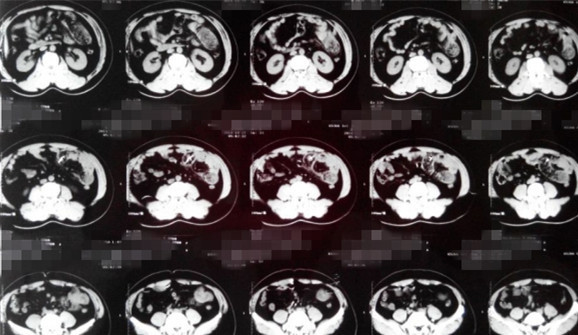

查体:腹部平软,左下腹轻压痛,未触及包块,肛门括约肌松弛,直肠内未触及异物,指套无染血。 辅查:腹部立位透视见左下腹部金属异物。腹部CT见下图。